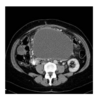

What dx?

pancreatic psuedocyst common complication of chronic pancreatitis